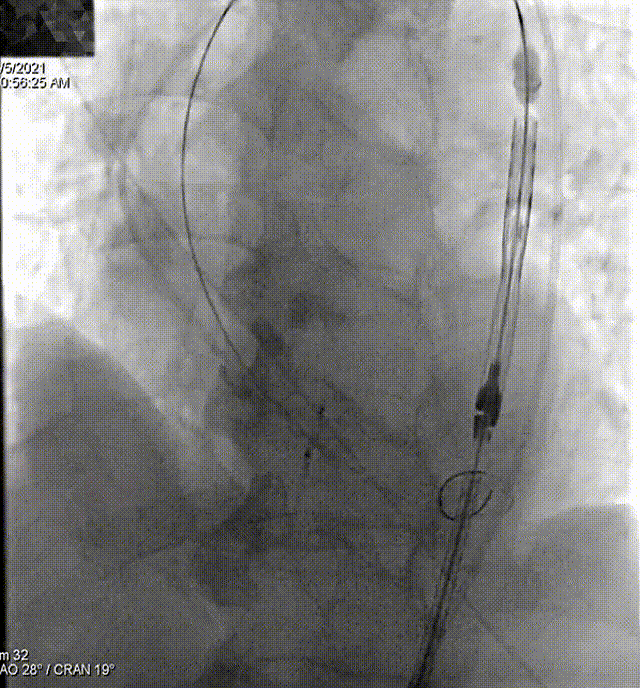

160次/min快速起搏下完成瓣膜释放,植入24 mm VitaFlow瓣膜

180次/min快速起搏下22 mm球囊行后扩处理

即刻超声评估示瓣周漏显著降低

最终释放效果

术后,患者跨瓣压差由术前的57mmHg降至术后1mmHg,仅少量瓣周漏。